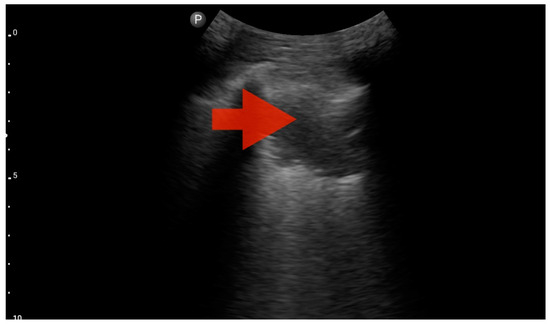

Profile B (BLUE protocol). Convex probe, top of the lung (2nd–3rd intercostal space), the red arrow indicates the vertical artifact of the B line (source: author’s material—DK).

Figure 9.